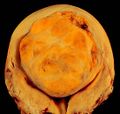

Fibroids are a type of uterine leiomyoma. Fibroids grossly appear as round, well circumscribed (but not encapsulated), solid nodules that are white or tan, and show whorled appearance on histological section. The size varies, from microscopic to lesions of considerable size. Typically lesions the size of a grapefruit or bigger are felt by the patient herself through the abdominal wall.[1]